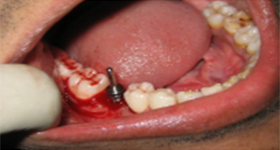

After a detailed planning phase which involves diagnostic impressions, radiographs and CT Scans, the dental implants will be placed into your jaw bone under local or general anesthesia. In certain conditions, we can go ahead and immediately restore these dental implants and you can walk out of the surgery with brand new teeth. In some cases, we will have to wait for a certain time period to ensure that the bone around the implant is healed before we replace the missing tooth or teeth.

We practice implant dentistry under local, general or sedation anesthesia. All of these options will be discussed at the time of your appointment.